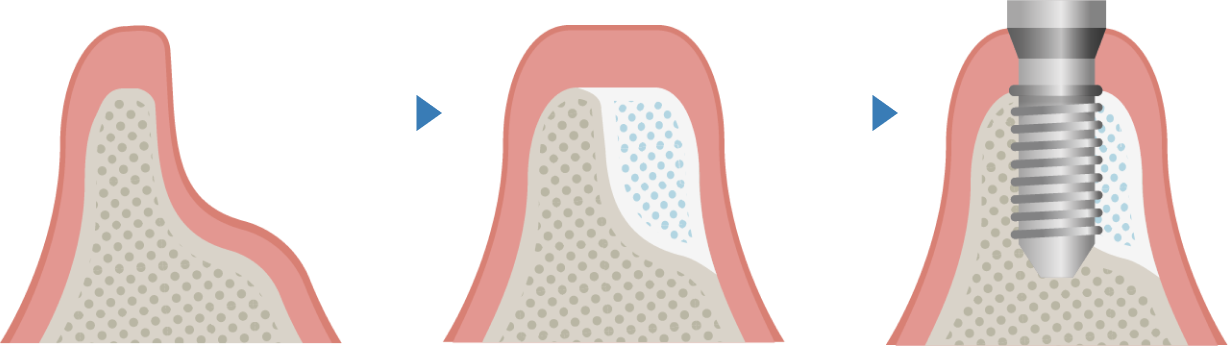

抜歯後、長期間放置したり、歯周病・破折による感染などにより骨が痩せてしまった場合、インプラントが難しくなることがあります。その場合、「骨造成」により骨の量を増やしインプラント体を埋め込むために必要な骨の厚みを確保します。ただし、移植する骨が多い場合や重篤な糖尿病などの全身疾患がある場合には処置が行えません。

骨造成には様々な術式があり、治療部位や残っている骨量によって、適した方法が異なっております。

GBR法とは、骨が不足している部分に人工骨や自家骨を塡入して、患部を特殊な膜(メンブレン)で覆うことで骨の再生を促す治療法です。

骨欠損の程度によってインプラント埋入と同時に行う場合と、GBR法により骨を増大してからインプラント埋入を行う場合があります。